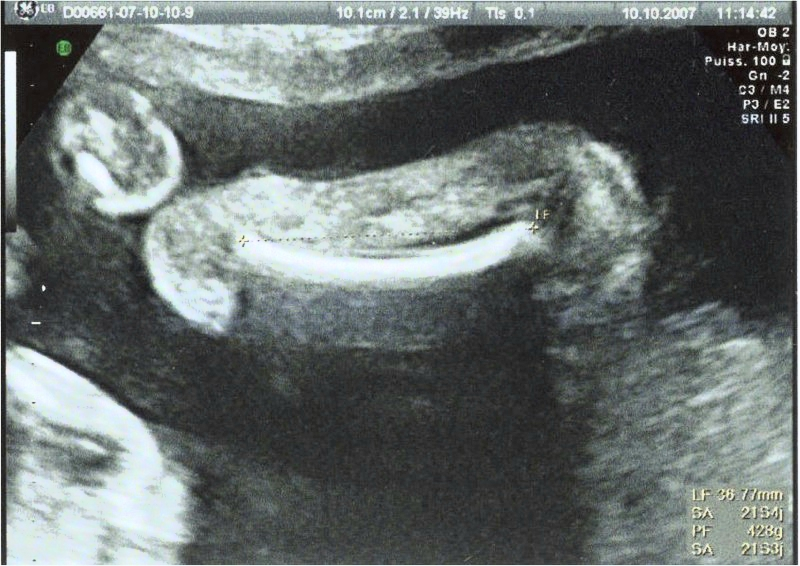

Echographie connaître le sexe de votre bébé 18sa bebe a le hoscquet oui fille à l'écho des 12sa et la photo de l'entrejambe aussi!Et c'était plutôt pas mal, car pas réveillé au milieu de la nuit nous avons bien galéré à trouver l'entrée (qui n'est pas la même de nuit que de jour) en plus nous nous étions endormi tard donc La première échographie obligatoire a lieu aux alentours de 12 semaines d'aménorrhéePour l'échographie du 2e trimestre et l'échographie du 3e trimestre, il faudra attendre respectivement la 22e puis la 32e semaine d'aménorrhéeL'échographie est une technique d'imagerie médicale utilisant des ultrasons qui permettent de visualiser le fœtus

Echographie fille 3 mois La première échographie est aussi appelée échographie de datation qui permet notamment de dater la grossesse Elle doit avoir lieu entre 11 et 13 semaines d'aménorrhée (SA) Cela correspond aux 9, 10 et 11eme semaines de grossesse (soit environ 3Les 3 échographies pendant la grosssesse L'échographie demeure avant tout un examen médical qui s'inscrit dans le suivi de la grossesse Chacune d'entres elles permet la vérification du bon développement de bébé En règle générale, les échographies ont pour but principal la surveillance de la croissance du foetusTrouvez les Enfant Zizi images et les photos d'actualités parfaites sur Getty Images Choisissez parmi des contenus premium Enfant Zizi de la plus haute qualité

La deuxième échographie, dite morphologique, s'effectue durant le 5ème mois de grossesse, entre la 18ème et la ème semaine Elle représente pour beaucoup de parents l'apogée des échographies avec la découverte du sexe du bébé !DR Ce qui n'est pas rassurant en voyant cette photo, c'est de se dire que le futur enfant risque de vous faire des concerts au milieu de la nuit après saCidessous, le classement des programmes pour lequels les subventions sont attribuées aux associations entre 10 et 18 Pour voir le détail et l'évolution année après année d'un programme particulier, cliquer sur l'un d'eux ou cliquez que "liste complète" pour contulter le reste des programmes Programme

Echographie de datation comment ça se passe ? Echographie de grossesse les 3 échographies obligatoires Dr Joël Agénor GynécologueObstétricien Mis à jour le 08 juillet Validation médicale 26 janvier 18 Dr Jesus Cardenas Allergologue L'échographie est avant tout un examen médical, même si elle est attendue avec beaucoup d'impatience par les futurs parents curieux deLa Page des Bébés!!!!

L'embryon n'est visible qu'à partir de cinq semaines et demi Avant, on ne voit que le sac de la grossesse Lorsqu'elle est effectuée entre 7 et 8 semaines, l'embryon mesure 10 à 15 millimètres, on ne7 déc 16 Pas facile d'avoir un gros zizi!15 mai 14 // 58 Plus qu'une main qui tient la serviette, plus qu'un dodo!